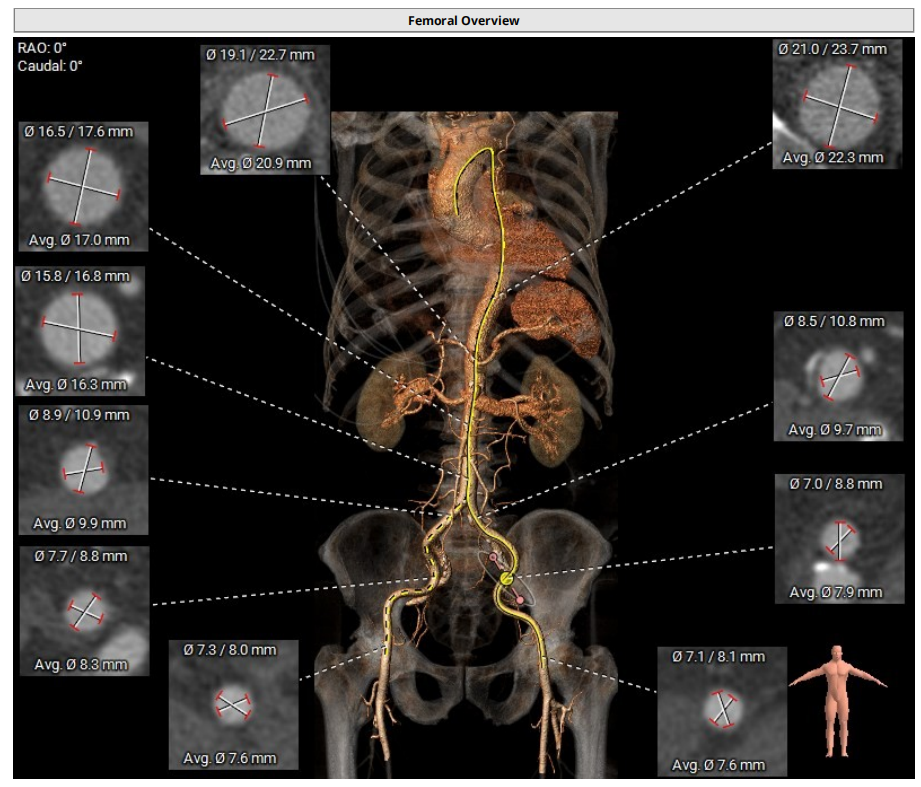

病例1:患者男性,70岁,三叶瓣。主动脉瓣重度狭窄,钙化集中于右冠窦、无冠窦,瓣环面积径23.3mm。左冠高度11.3mm,右冠高度16.1mm。外周入路可见钙化,内径尚可。

术中经右侧股动脉入路,使用19mm球囊预扩,顺利植入23# RENATUS®球扩式经导管主动脉瓣,瓣膜释放位置理想、形态及功能良好,无外周血管损伤,术后无瓣中及瓣周反流等并发症。

手术团队术前经充分的食道超声及心脏CTA详尽评估患者病情、外科手术风险,通过CT重建测量瓣环直径、左室流出道面积、房间隔穿刺位置等确定手术策略与解剖入路,最终决定采用二尖瓣经导管瓣中瓣手术,选择瓣架较短,可应用于各个不同瓣位的RENATUS®球扩式经导管主动脉瓣。

患者既往植入27# 佰仁思牛心包瓣,选用27# RENATUS®球扩式经导管主动脉瓣,术前模拟植入测得Neo-LVOT面积217.3mm²。